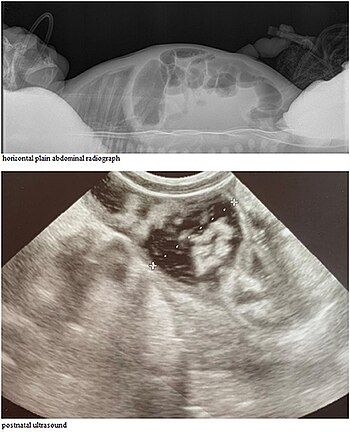

Abdominal ultrasound exam shows significantly distended intestinal loops of newborn

CCD may be detectable on prenatal ultrasound.[4][5]